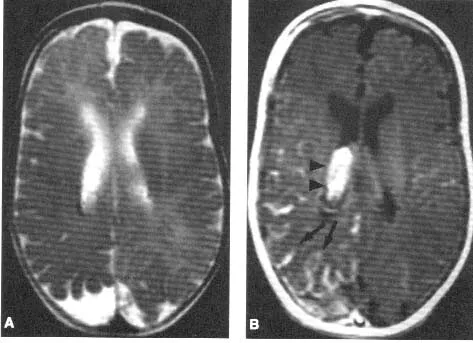

- Chụp cộng hưởng từ (MRI): Đây là phương pháp chính để xác định các bất thường mạch máu trong não.